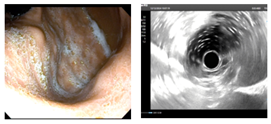

周末在家鄉(xiāng)縣醫(yī)院與當(dāng)?shù)蒯t(yī)生協(xié)作完成一例考慮胃間質(zhì)瘤內(nèi)鏡下EFTR術(shù)(全層切除術(shù))?;颊呶哥R查出2-3cm黏膜下隆起,質(zhì)地較韌,胃內(nèi)此種病變絕大多數(shù)考慮間質(zhì)瘤。因當(dāng)?shù)乜h醫(yī)院超聲內(nèi)鏡購(gòu)買中,還未到位?;颊哂值膺^(guò)敏,因此術(shù)前只能行上腹部CT平掃,充分喝水撐開(kāi)胃腔后,瘤子輪廓較清晰。溝通交流后,家屬充分信任,考慮內(nèi)鏡下微創(chuàng)切除。手術(shù)非常順利,瘤子完整切除,避免了外科腹腔鏡/開(kāi)腹手術(shù)。術(shù)后病灶性質(zhì)明確及是否需要進(jìn)一步靶向藥口服等有待進(jìn)一步病理評(píng)估。結(jié)合病例診療談?wù)剮c(diǎn)感悟:1.充分的術(shù)前評(píng)估很重要,有時(shí)候不可能裝備精良,那也得用好手頭已有的武器,此例患者沒(méi)有做超聲內(nèi)鏡條件,術(shù)前CT評(píng)估做得很漂亮,患者自身準(zhǔn)備的好,水喝的很足,病灶顯示也很清楚。2.多與相關(guān)科室進(jìn)行討論,術(shù)前與兄弟科室普外科交流討論,明確手術(shù)適應(yīng)癥、禁忌癥。做好多種方案,有備無(wú)患。3.與患方多溝通交流,解答對(duì)方困惑,建立良好醫(yī)患信任?;挤椒菍I(yè)人士,難免有困惑及焦慮。淺顯易懂將治療相關(guān)原理與可能發(fā)生情況及應(yīng)對(duì)策略告知他們后,不但有助于他們解除困惑及焦慮,也有助于建立和諧醫(yī)患關(guān)系。4.引用我科熊光蘇主任科普相關(guān)文@消化內(nèi)鏡熊光蘇醫(yī)生。消化道疾病提倡早診治療,以胃腸道間質(zhì)瘤為例。絕大部分小瘤子(小于1cm)可以選擇定期內(nèi)鏡隨訪,但是越大的瘤子,惡變風(fēng)險(xiǎn)越大(量變引起質(zhì)變),較大的瘤子還是建議切除,具體是內(nèi)鏡還是外科還需具體評(píng)估。5.對(duì)于一些交界性大小病變(例如1cm左右的),切還是不切的糾結(jié)問(wèn)題。我個(gè)人建議是:綜合年齡及患者個(gè)人心態(tài),如果能夠接受定期復(fù)查不想切,可以選擇隨訪。如果心態(tài)上就有定時(shí)炸彈????思想,那還是早點(diǎn)前往權(quán)威醫(yī)院尋求經(jīng)驗(yàn)豐富醫(yī)生行切除治療,一勞永逸。